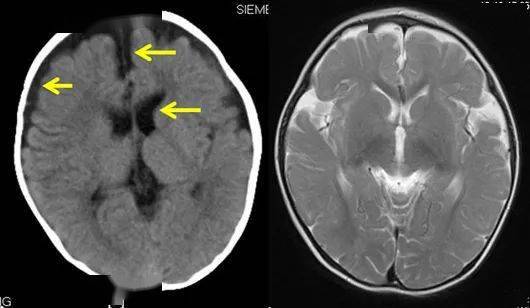

脑水肿会出现什么症状

脑水肿早期症状主要包括以下几点头痛由于颅内压增高,脑膜血管和脑神经受到牵拉和炎性改变刺激,导致头痛起初为阵发性,后发展为持续性,以前额和双颞侧为主,轻重不等在咳嗽打喷嚏用力大便弯腰或起立时头痛加重,严重时会有类似撕裂...